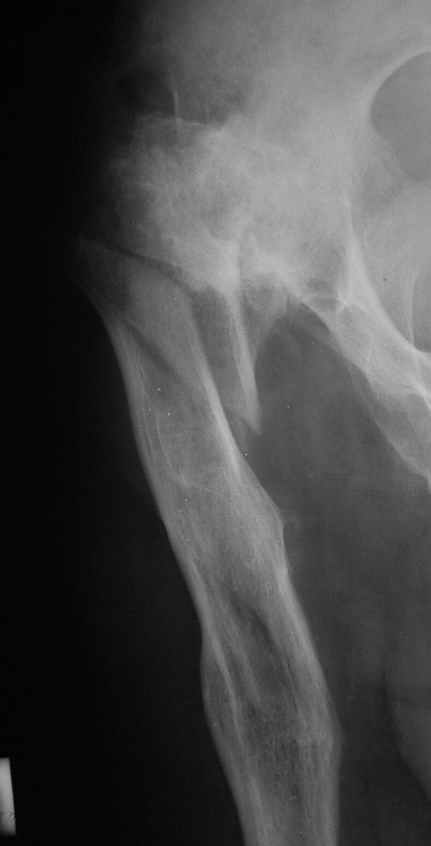

Рентгенограммы до и после. Больной профессор на кафедре сопромата и после детального изучения

особенностей имплантата, собственных рентгенограмм дал добро на операцию. Ваш вариант лечения вполне симпатичен.

С уважением А.Семенистый.